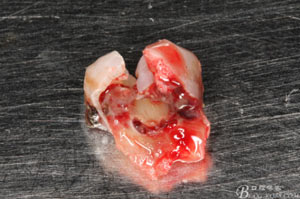

圖7.37牙冠碎裂。多生牙壓迫吸收程度嚴(yán)重。

圖8.拔除的37頰側(cè)的牙根完全被壓迫吸收完

圖9.清理牙槽窩過(guò)后。多生牙的牙冠暴露在牙槽窩內(nèi)。